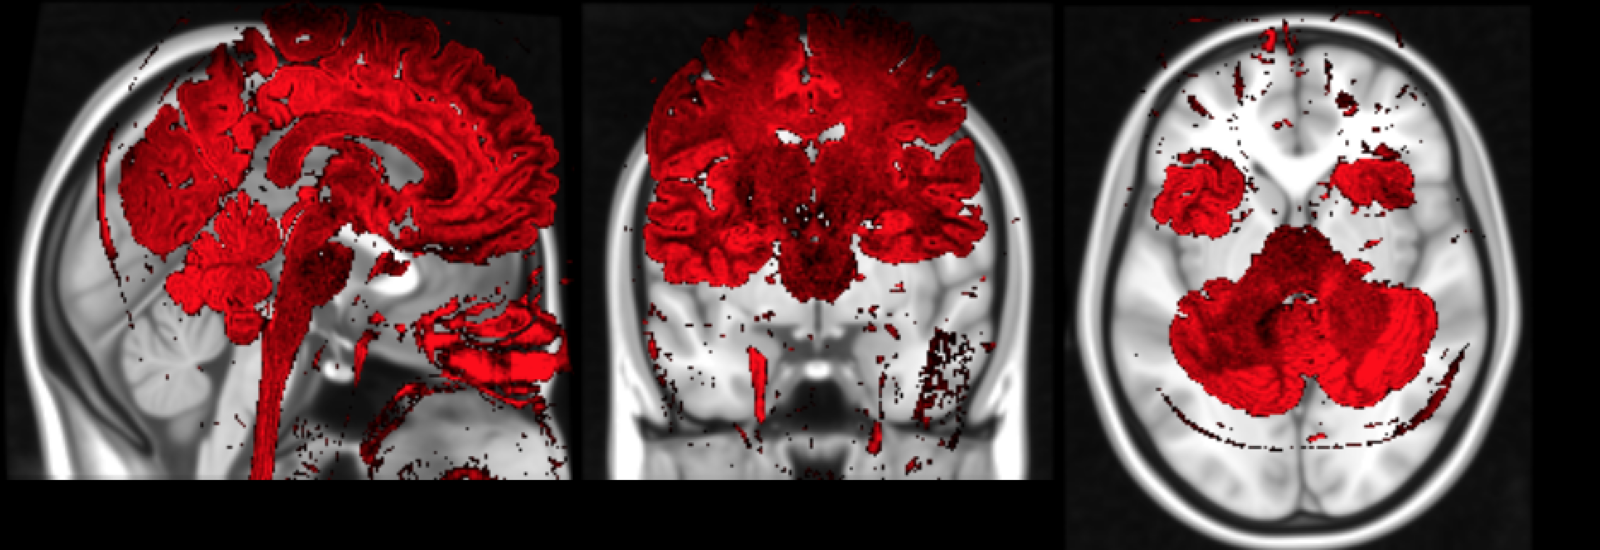

3. Cortical Lesion Filling

Lesion filling algorithms in MS try to inpaint T1 hypo-intense WM lesion (about 30% of FLAIR-appearing lesions) as Normal-Appearing White Matter (NAWM).

This procedure has shown to improve:

- Segmentation reliability

- Cortical Thickness estimation in longitudinal studies.

This procedure has NOT been studied before over Cortical Lesions: only ~15% appear as hypo-intense in T1.